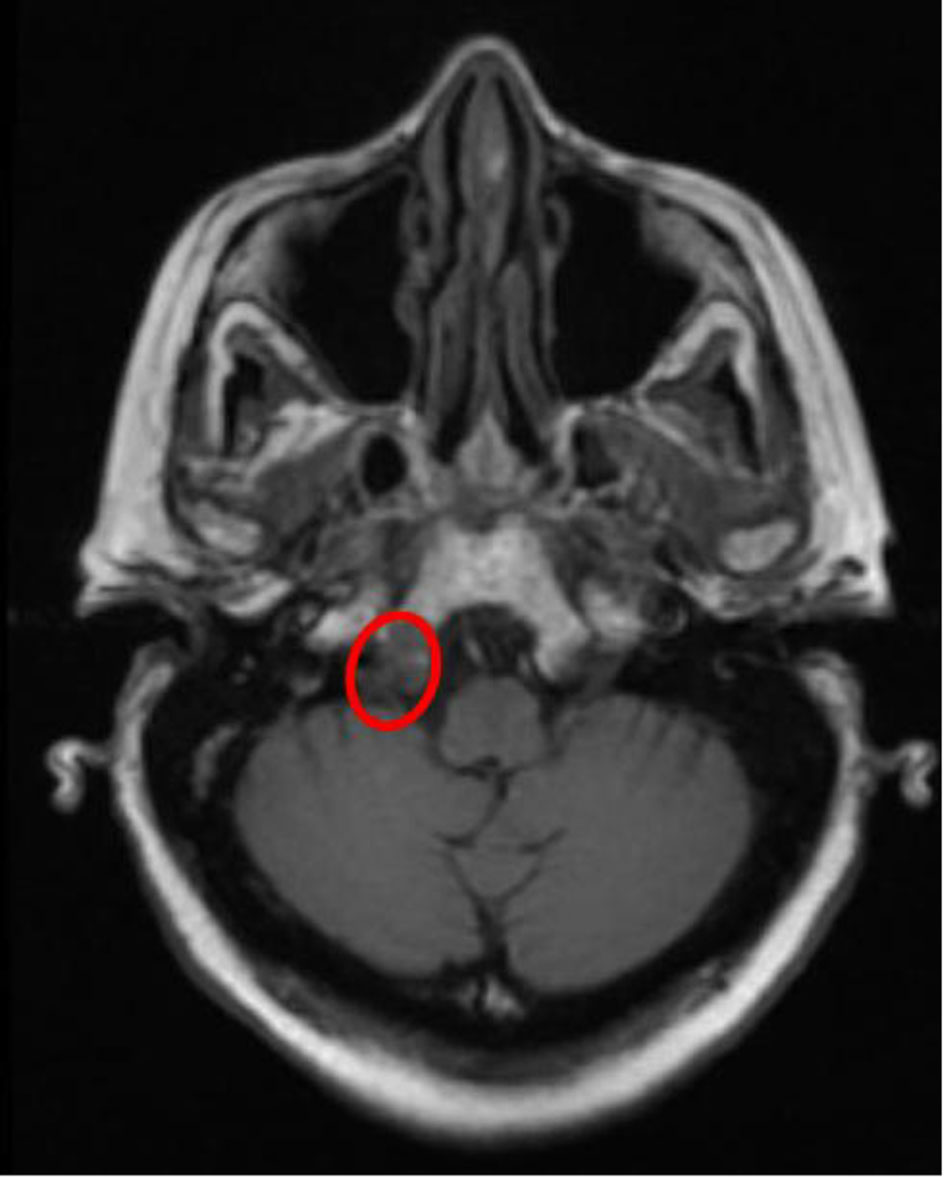

The skeletal survey seen in Figure 1 demonstrated the significant progression of her disease, especially near the skull base. Magnetic resonance imaging (MRI) of her brain, seen in Figure 2, revealed that the patient had myelomatous lesions at the right occipital condyle and clivus consistent with MM disease advancement. The cause of her dysarthria was concluded to be hypoglossal nerve mononeuropathy, due to impingement as the nerve courses through the hypoglossal canal, located at the base of the right occipital condyle. Although the patient did understand that all of her conditions stemmed from poorly controlled disease, she did not desire to pursue further chemotherapy or receive blood transfusions at the time.

![]() Click for large image | Figure 2. Eroded occipital condyle affecting the hypoglossal nerve. |

Untreated MM can have several serious side effects as this case reveals. MM causes severe osteolytic destruction via cytokines, specifically IL-1, which then activates RANK-L on osteoclasts [9]. When the disease is markedly uncontrolled, as was revealed in this case, there is marked bone remodeling and lysis throughout the body. Impingement of the hypoglossal nerve causing mononeuropathy at the occipital condyle has been reported in association with condyle fracture [10]. Furthermore, a review article focusing on MRI of the course of the hypoglossal nerve demonstrates how any interruption of the nerve course at the clivus or condyle due to pathologies such as bone destruction or tumor invasion leads to the mononeuropathy [11]. Similarly, this patient had severe osteopenia and marrow involvement at both the right clivus and right occipital condyle. This involvement directly explains the right-sided (lower motor neuron) pathology visualized on exam.